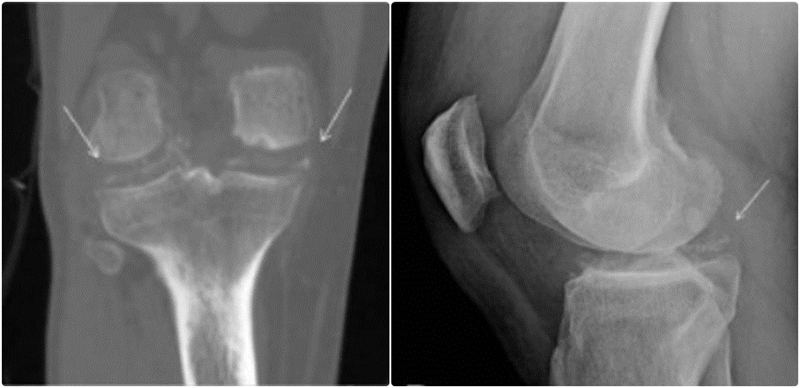

图1.受累部位呈点状、线状或斑片状钙化影(受累部位钙化所致),以及受累关节间隙间隙变窄,并可伴骨赘形成